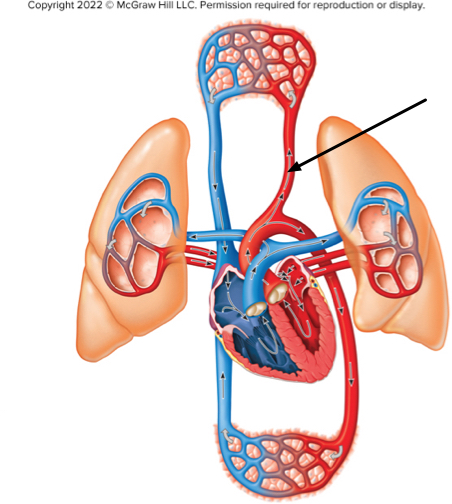

What type of blood is at the location indicated by the arrow?

oxygenated blood of the systemic circuit